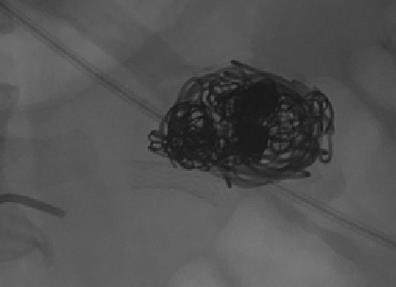

肾动脉瘤填塞

|

|

|

|

|